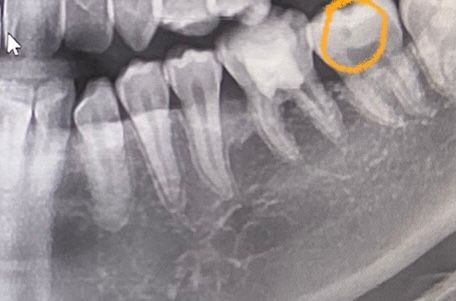

두번째 사진의 치아는 인접면 충치일까요? 인접면이 살짝 어두운데 충치인가요?

충치는 파노라마로 판별하지는 않습니다. 치근단사진과 임상검진을 같이 하여 판별해야합니다.

저부위가 무조건 충치라고 말씀드리기는 어려울것같습니다. 일단 육안으로도 판단을 해봐야될것같습니다.만약 저부위가 충치가 맞다면 충치가 상당히 깊은곳에 위치하는것이며 충치를 제거하는과정중에 신경이 뚤리면 신경치료를 해야될 가능성이 높습니다.